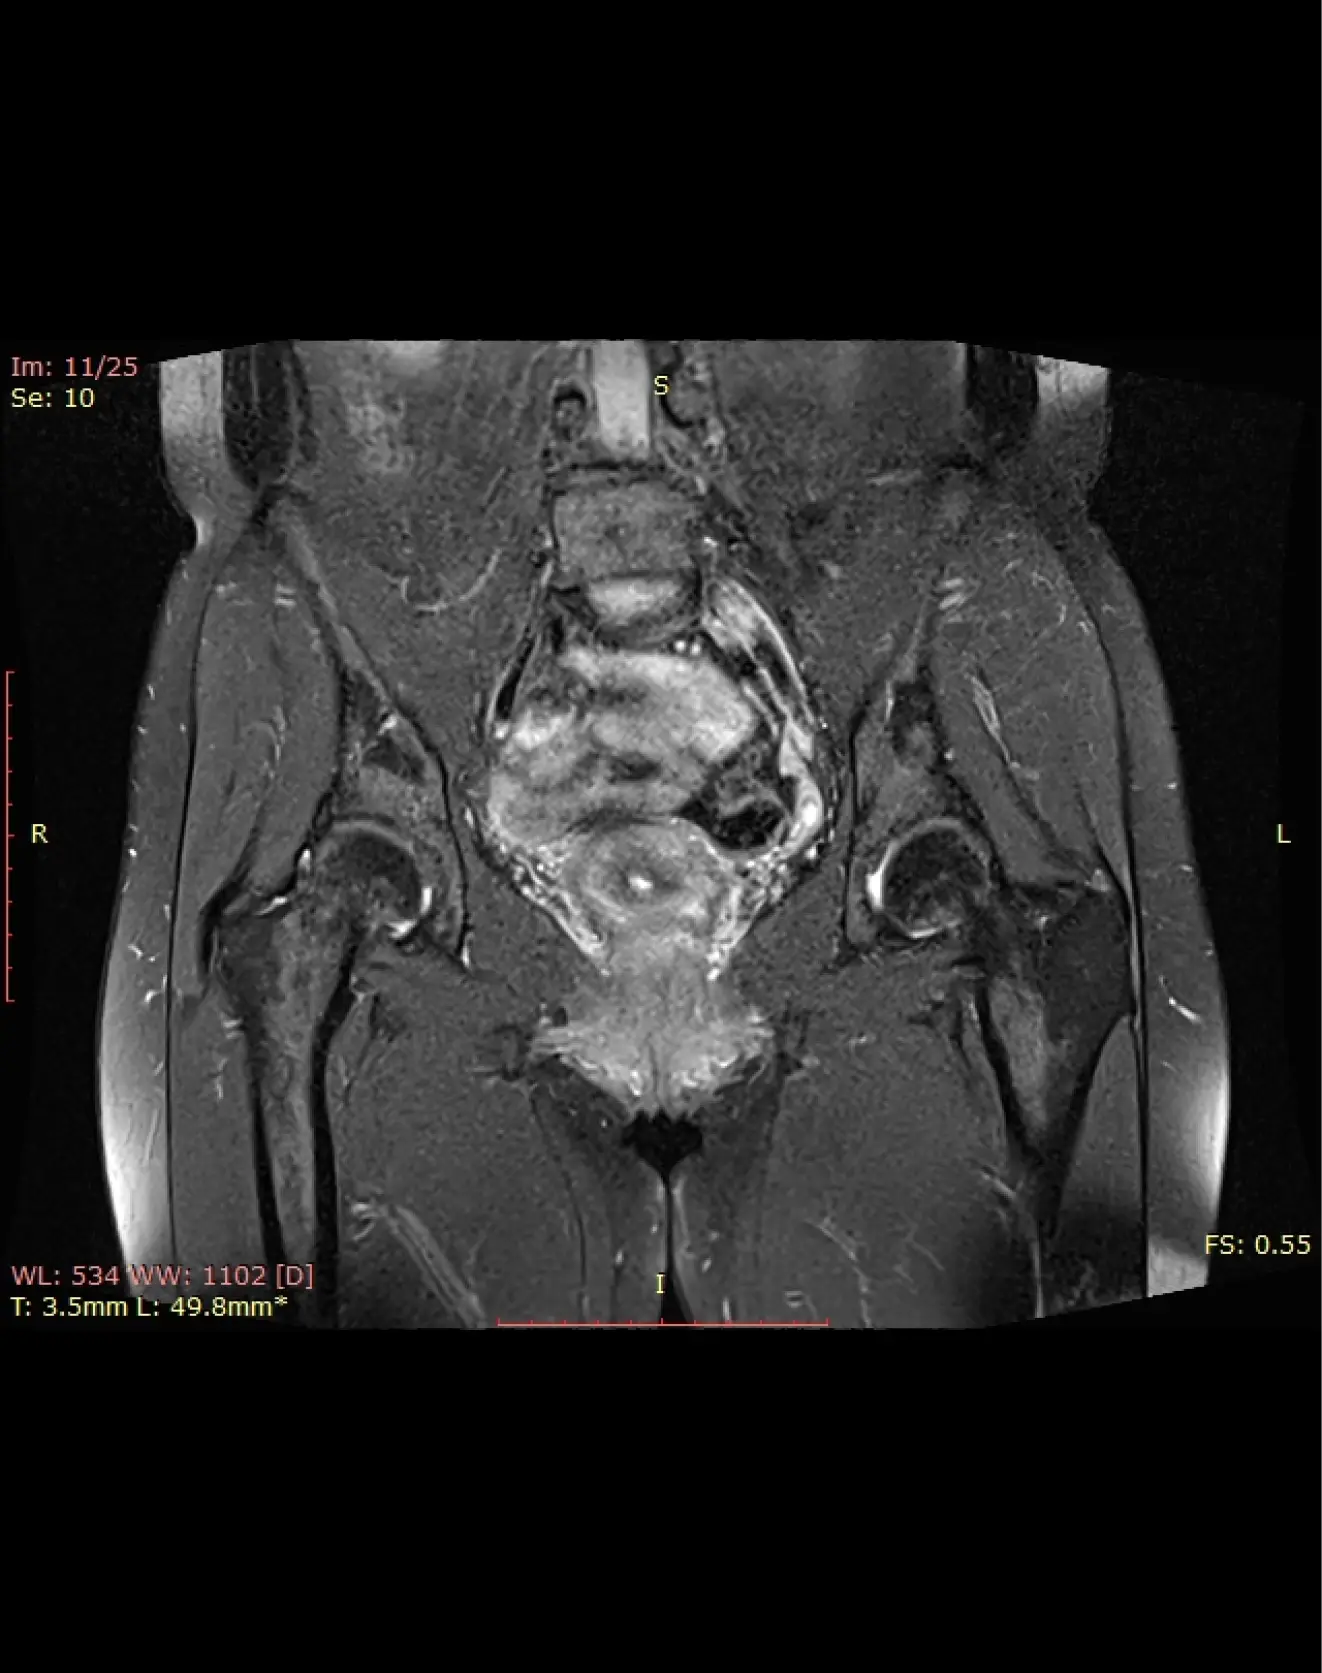

МРТ тазобедренного сустава (пара)

Визуализация костей тазобедренного сустава, суставная губа, суставная капсула, параартикулярные ткани.